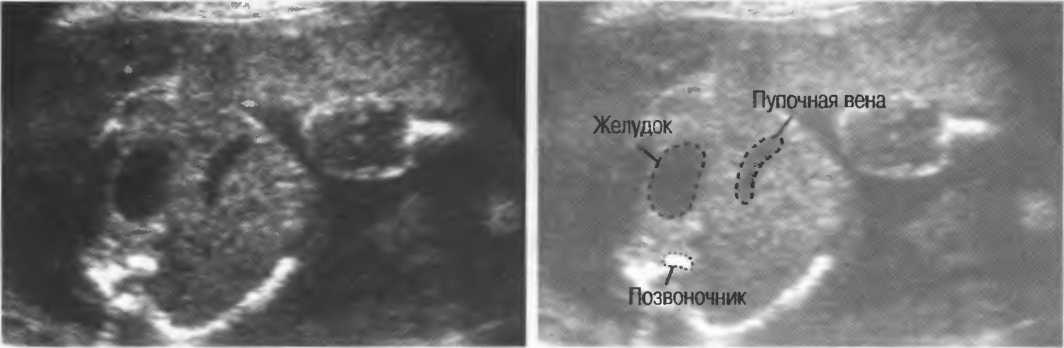

- При удовлетворительном качестве изображения можно получить изображение полости прозрачной перегородки головного мозга у 35-недельного плода (рис. 23). Этот тест можно использовать для контроля качества в случаях, когда нет фантома. Данный тест необходимо проводить каждые 3 мес.

Рис.23а. На любом приборе должна визуализироваться полость прозрачной перегородки головного мозга 35-недельного плода.

Рис.23б. На аппарате высокого класса полость может визуализироваться в более ранние сроки беременности.

2. Верхняя брыжеечная артерия должна визуализироваться в виде округлого или овального эхонегативного образования, расположенного рядом с поджелудочной железой у здорового взрослого обследуемого (рис. 24). Наиболее простым способом проверки качества изображения является визуализация своей собственной верхней брыжеечной артерии. Сохраняйте эхограммы после каждого исследования для сравнения.

Рис.24. Поперечный срез: верхняя брыжеечная артерия представлена эхонегативным округлым образованием, окруженным эхогенной жировой клетчаткой, расположенным близко к поджелудочной железе.

- Печеночные вены диаметром всего 3 мм должны визуализироваться при сканировании под углом 45° к поверхности нормальной печени (рис. 25).

Рис.25. Аппарат хорошего качества должен позволять визуализировать печеночные вены диаметром 3 мм. Этот тест может регулярно использоваться для контроля качества изображения.

4. У здоровых обследуемых паренхима печени должна быть немного более эхогенна. чем кора рядом расположенной почки (рис. 26).

Рис.26. Продольный срез через печень и правую почку: нормальная паренхима печени более эхогенна, чем паренхима нормальной почки. Это еще один способ проверки качества изображения.